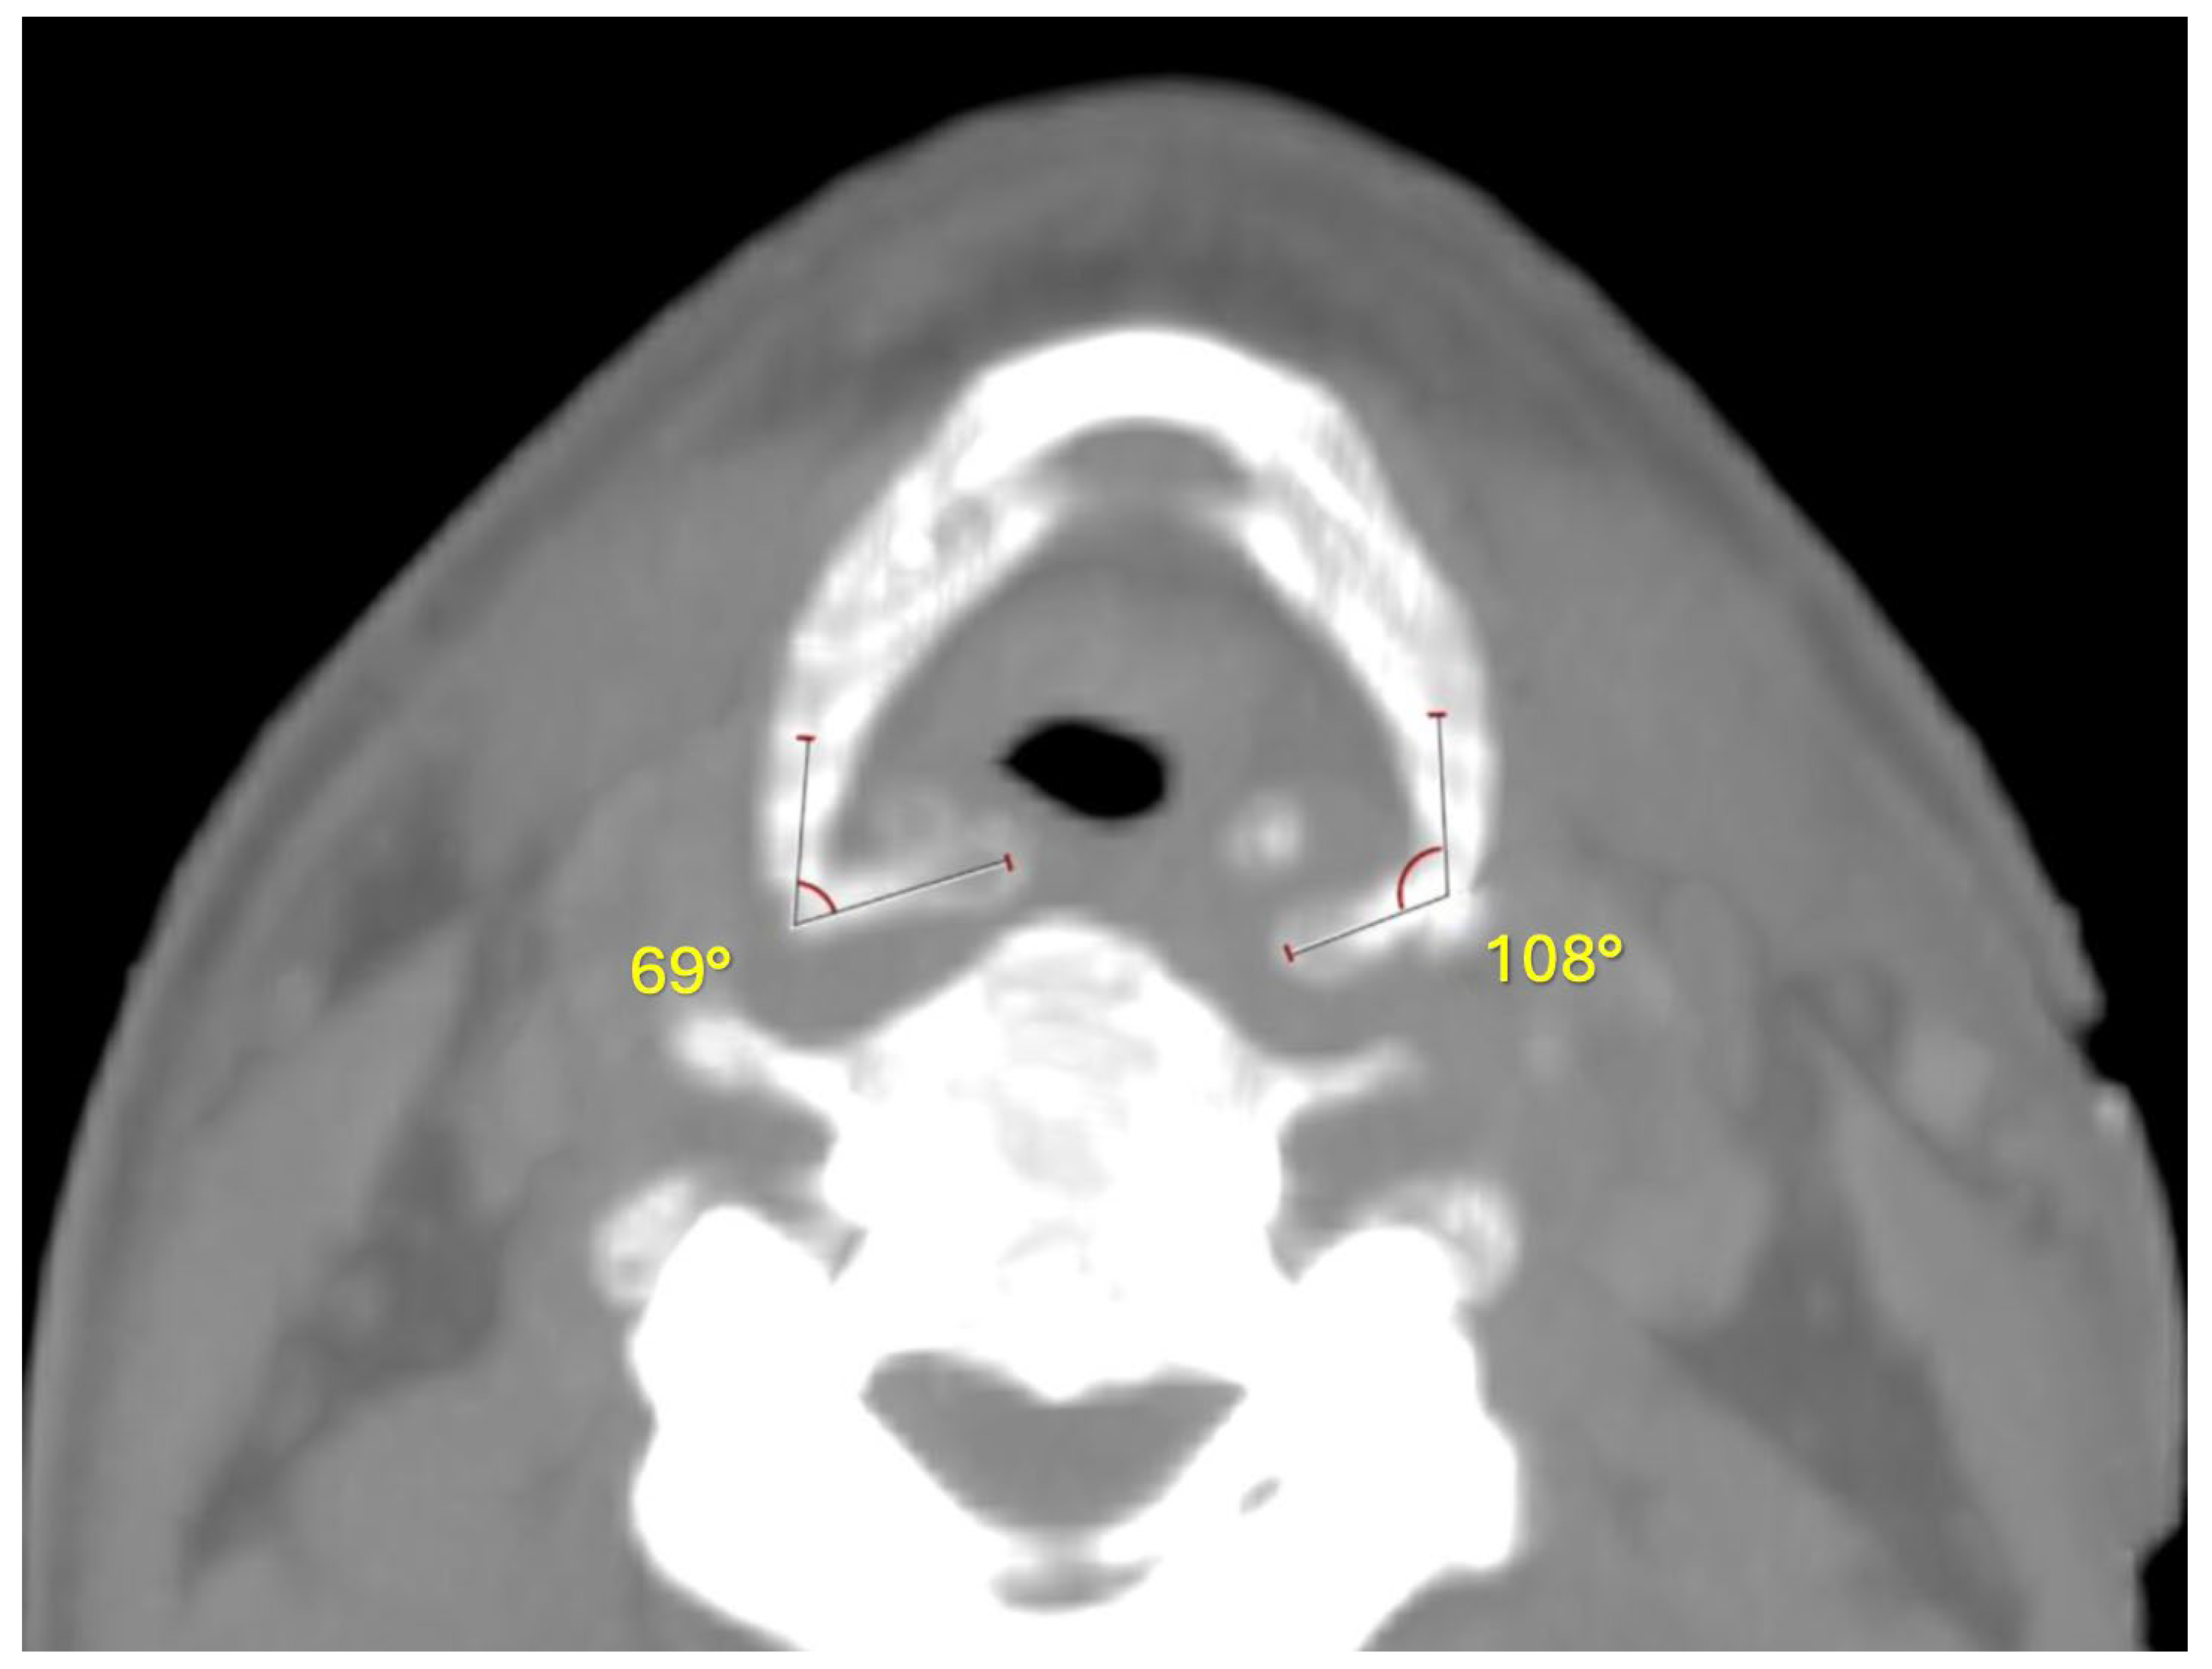

2. Case Report